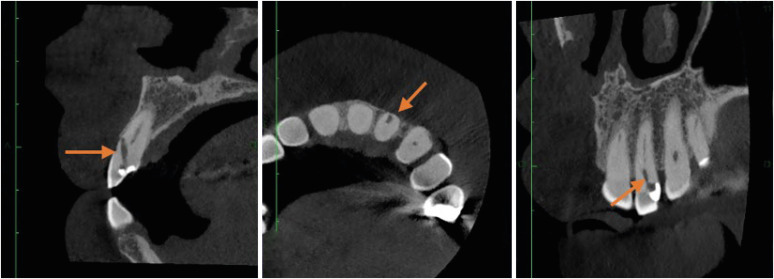

研究目的本研究旨在通过锥形束计算机断层扫描(CBCT)分析,调查牙髓治疗程序错误的频率和类型:样本包括 96 张 CBCT 扫描图,涵盖 122 颗牙根完全成形的恒牙。误差包括穿孔、器械折断、牙槽移位、遗漏牙槽和根尖充填极限不足。此外,还对潜在的风险因素进行了分析和统计建模:结果:最常见的程序错误是根尖充填极限不足,其次是根管运输、穿孔、遗漏根管和器械折断。各种程序错误与特定因素之间存在明显的统计学关联。这些因素包括:根管运输和根管壁,其中颊侧壁最常受到影响;遗漏的根管和牙齿类型,尤其是腭侧和第二中颊面管;根尖充填限值不足和根弯曲度,显示出严重弯曲的根管向中侧方向的偏差更大;根尖充填不足和存在钙化,其中以充填不足最为常见;根管运输和根尖周病变,特别是偏向颊侧方向;以及穿孔方向和根尖周病变,其中以偏向颊侧方向最为常见。结论:CBCT 是识别程序错误和相关因素的重要工具,对预防和管理这些错误至关重要。

Materials and methods: The sample consisted of 96 CBCT scans, encompassing 122 permanent teeth with fully formed roots. Errors included perforation, instrument fracture, canal transportation, missed canals, and inadequate apical limit of filling. Additionally, potential risk factors were analyzed and subjected to statistical modeling.

Results: The most frequent procedural error observed was the inadequate apical limit of filling, followed by canal transportation, perforation, missed canal, and instrument fracture. Statistically significant associations were identified between various procedural errors and specific factors. These include canal transportation and root canal wall, with the buccal wall being the most commonly affected; missed canal and tooth type, particularly the palatine and second mesiobuccal canal canals; inadequate apical limit of filling and root curvature, showing a higher deviation to the mesial direction in severely curved canals; inadequate apical limit of filling and the presence of calcifications, with underfilling being the most frequent; canal transportation and periapical lesion, notably with deviation to the buccal direction; and the direction of perforation and periapical lesion, most frequently occurring to buccal direction.